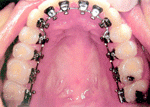

มาถึง การจัดฟันด้านใน

การจัดฟันแบบใสและขั้นตอนการจัดฟันมีรูปคนน่ารักจัดฟันด้วย    การจัดฟันแบบใสและขั้นตอนการจัดฟันมีรูปคนน่ารักจัดฟันด้วย       การจัดฟันแบบใสและขั้นตอนการจัดฟันมีรูปคนน่ารักจัดฟันด้วย

การจัดฟันแบบใสและขั้นตอนการจัดฟันมีรูปคนน่ารักจัดฟันด้วย   >>  การจัดฟันแบบใสและขั้นตอนการจัดฟันมีรูปคนน่ารักจัดฟันด้วย  >> การจัดฟันแบบใสและขั้นตอนการจัดฟันมีรูปคนน่ารักจัดฟันด้วย

>>   การจัดฟันแบบใสและขั้นตอนการจัดฟันมีรูปคนน่ารักจัดฟันด้วย     >>>>>>>  การจัดฟันแบบใสและขั้นตอนการจัดฟันมีรูปคนน่ารักจัดฟันด้วย